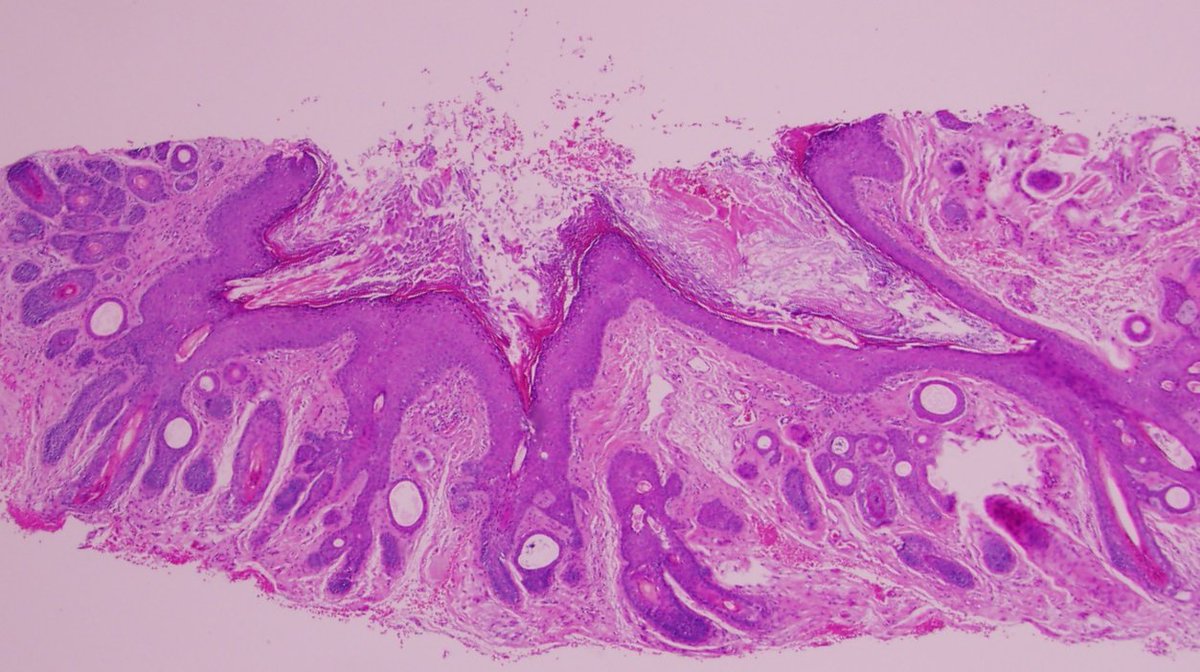

Beatiful ghost cells

Dermnemonics tweet media